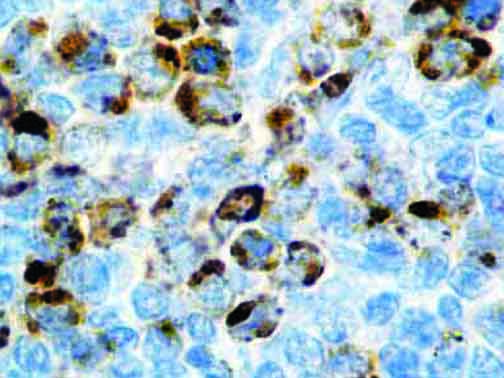

It is the ICU physician who is most likely to witness one of the deadliest manifestations of the abnormal immunological response, the cytokine storm syndrome (CSS). This response is also referred to by some as the cytokine release syndrome (CRS). CSS is characterized by continuous activation and expansion of macrophage and lymphocyte populations, which secrete large amounts of cytokines, causing the cytokine storm. This massive cytokine release is akin to hemophagocytic lymphohistiocytosis (HLH) disease, a syndrome characterized by initial unchecked and persistent activation of cytotoxic T lymphocytes and NK cells.

Clinical and laboratory manifestations of HLH include fever, enlarged liver and/or spleen, neurologic dysfunction, coagulopathy, liver dysfunction, cytopenias (i.e., low levels of erythrocytes, leukocytes, and/or platelets), hypertriglyceridemia, hyperferritinemia, hemophagocytosis, and eventually diminished NK cell activity as the immune system becomes progressively paralyzed. HLH can be familial (primary HLH) or secondary to another disease process (sHLH), such as rheumatic disease, in which it is referred to as macrophage activation syndrome (MAS, characterized by elevated ferritin).